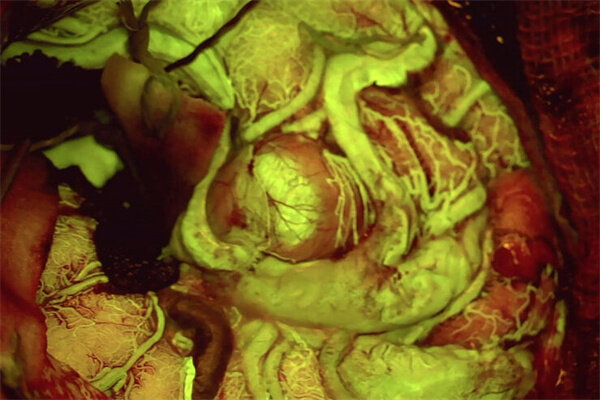

徕卡神经外科手术显微镜采用创新的集成技术,通过增强现实 (AR) 技术增强术者的视觉效果。  例如在脑血管外科手术中,GLOW800 增强现实荧光 (AR 荧光) 可实现血流的实时清晰可视化。

使用 GLOW800 可视化进行微创手术夹闭未破裂的大脑中动脉(MCA)和后交通动脉(PCOM)动脉瘤治疗。

脑血管手术 — 一张增强视图

GLOW800 增强现实荧光 (AR 荧光) 和 ICG 吲哚箐绿造影剂搭配使用,可以呈现出一张白光和荧光效果同时存在的实时血流视图,在颅脑解剖结构和血流之间形成清晰可见的轮廓。

这项先进的功能可在一张视图中同时呈现色彩自然的颅脑解剖结构和实时血流,不必中断手术过程在自然的显微镜图像和平面黑白近红外视频之间来回切换。

查看色彩自然的组织,全面感受深度知觉,并获取实时增强的血流视图,在脑血管手术中更加自信地作出准确的治疗决策。

GLOW800在动脉瘤修复中的应用